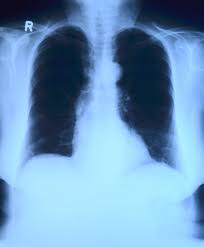

자기를 증명 할 수 있는 신분증 즉 주민등록증이나 운전면허증을 가지고 거주지 관할 보건소 방문해서 검사받을 수 있습니다. 검진 방법은 보건소 방문하셔서 흉부X선 검사를 받은 후 결핵 의심이 해당 된다고 판단되면 판단되면 확진 검사를 하게 됩니다. 거주지 관할 보건소 위치를 알려면 '거주지' 관할 보건소 확인 페이지'를 통해서 확인이 가능합니다.

✅ 2주 이상 기침을 하는 사람은 반드시 건강진단을 받는다. (X-ray 관찰)